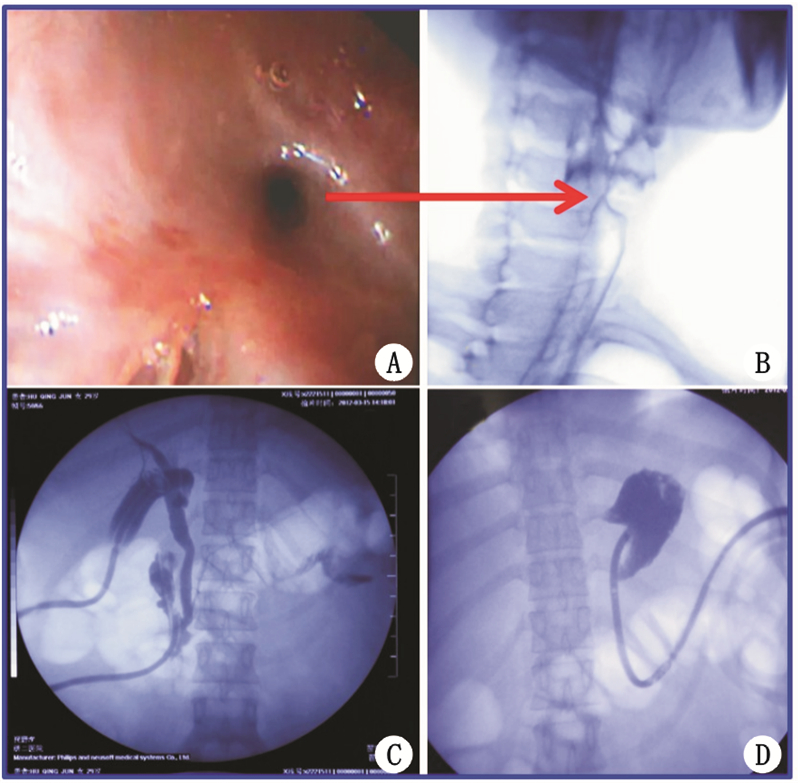

患病2个月后出现食管起始部狭窄(A:胃镜,B:食道造 影),胃流出道(C、D:胃肠造影) 狭窄 图 4 浓硫酸腐蚀导致后期食道起始部及胃流出道狭窄